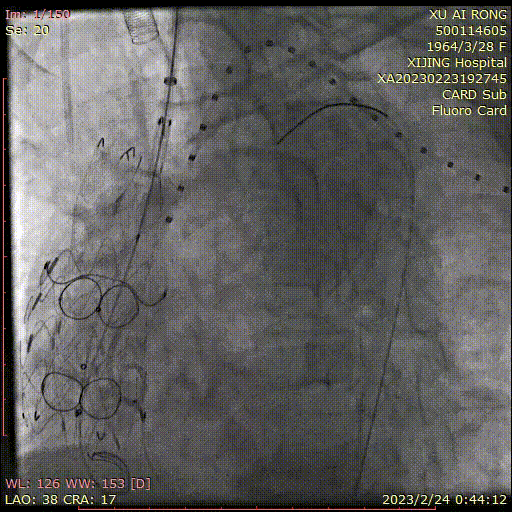

★ 病例4

王某,女,56岁,“突发胸背痛15小时”入院,主动脉CTA提示:升主动脉-腹主动脉管腔外可见新月形低密度影,主动脉弓前部可见溃疡,大小约0.6cm。

术前CTA

术前造影

术后造影

手术用时 95分钟